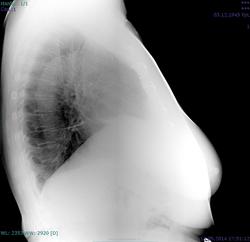

Пациентка 1945 г.р. Флг для ВТЭК, жалоб особых нет, температура нормальная, дыхание свободное. Архив от 2010 - без особенностей. В начале апреля 2014 г АКШ, согласно выписке R перед операцией - без особенностей, после операции - отмечалось высокое стояние пр купола диафрагмы. Самих снимков нет. Дисковидный ателектаз в S9 справа, тень с четкой верхней границей (в медиальных её отделах) над диафрагмой на прямом - признаки гиповентиляции? Или тень - плевральные наложения? Требуется ли контроль\дообследование?

Состояние после стернотомии.Линейная тяжистость в нижней доле справа( фиброз). Релаксация правого купола диафрагмы.( Дообследование не требуется).

Я считаю, плевродиафрагмальной швартой ( гляньте на боковой. Или стрелку рисовать?)

ХЗ, скиалогия какая-то, может организовавшаяся жидкость в междолевой щели.

Это вполне может оказаться жидкость с заходом в нижние отделы главной м/долевой щели, уже осумкованная,и в малом количестве. Базальные сегменты поджаты( дисков. ателектаз) -горизонт. тень. Со временем все рассосется.Но купол останется высоким, если не "раздышится".При R-контроле все увидите.